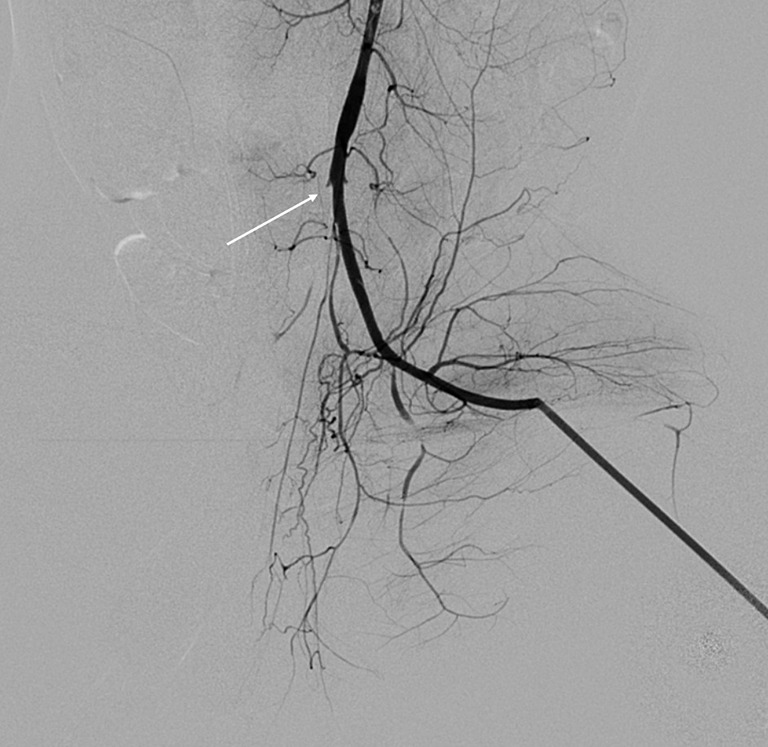

Methods: Acute ischemia models were established in 25 New Zealand white rabbits through arterial ligation of their right hind legs. Magnetic resonance imaging (MRI) examinations of the vastus lateralis muscle were conducted hourly postsurgery for a duration of 7 hours. The scan sequences included IVIM, adenosine triphosphate (APT), T1-weighted imaging (T1WI), T2-weighted imaging with fat suppression (T2WI-FS), T2 mapping, and diffusion-weighted imaging (DWI). The correlations between MRI results, ischemic time, and pathological changes were analyzed.